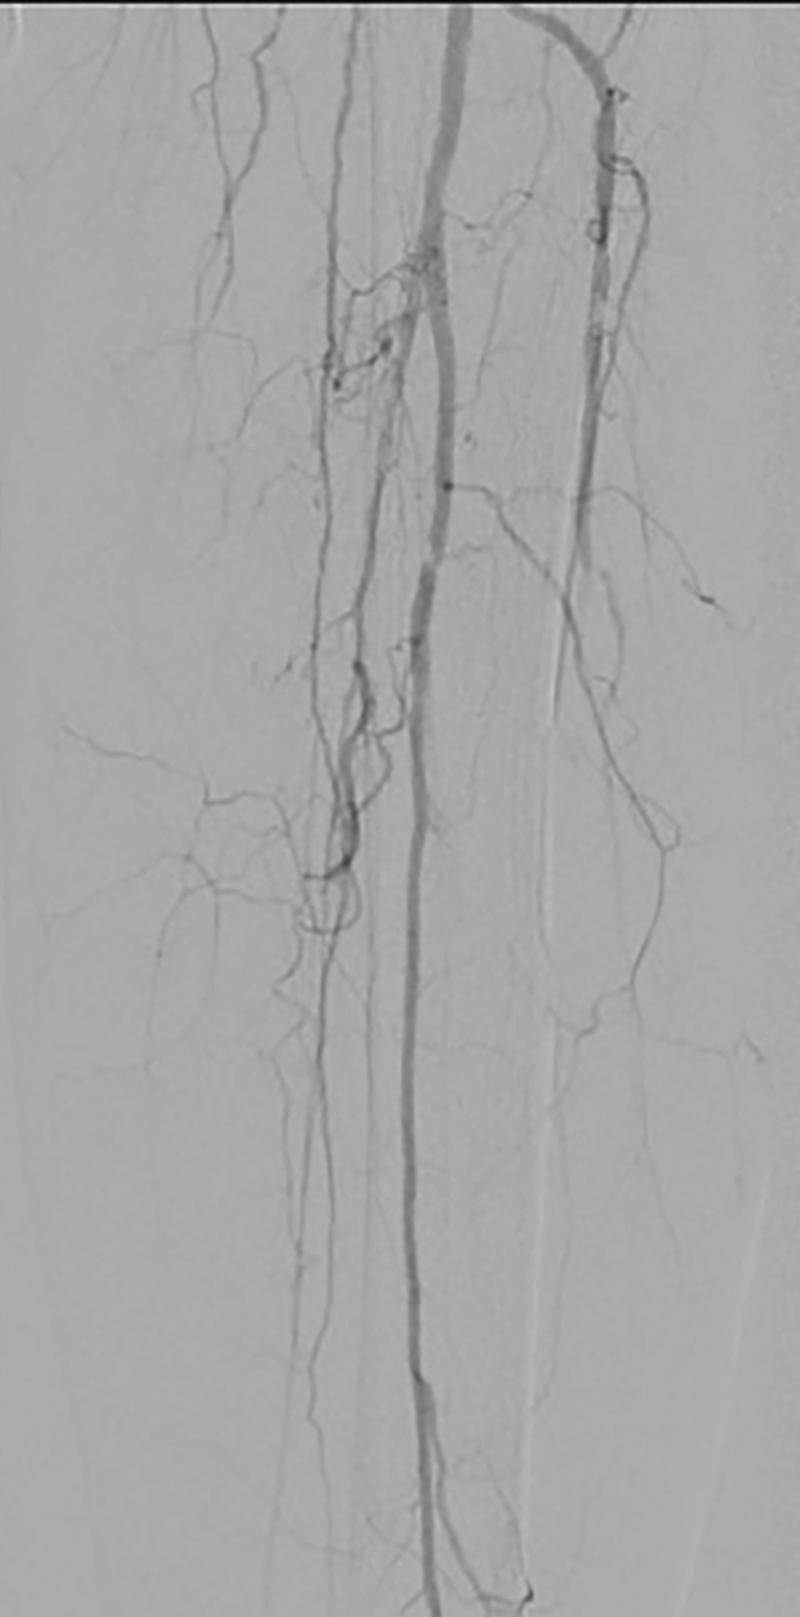

Distal lower extremity wounds are a challenging problem for reconstructive surgeons and can lead to major lower extremity amputations in patients with comorbid conditions. The reverse sural artery flap (RSAF) is a local flap supplied by perforators of the peroneal artery that can cover defects of the distal lower extremity, ankle, and foot. There has been concern over performing the RSAF in patients with venous insufficiency, peripheral artery disease, and diabetes, and in older patients due to the increased risk of flap necrosis. In patients who are not microsurgical candidates, the RSAF may be the final option for reconstruction before undergoing major lower extremity amputation. We describe our experience with two patients with significant comorbidities and single vessel runoff from the peroneal artery due to atherosclerotic disease who successfully underwent RSAF reconstruction for distal lower extremity wounds.

下肢远端伤口对于重建外科医生而言是个具有挑战性的问题,并且在患有合并症的患者中可能导致下肢大截肢。腓肠神经营养血管逆行皮瓣(RSAF)是一种由腓动脉穿支供血的局部皮瓣,可覆盖下肢远端、踝关节和足部的缺损。由于皮瓣坏死风险增加,对于患有静脉功能不全、外周动脉疾病和糖尿病的患者以及老年患者进行RSAF手术一直存在担忧。在不适合进行显微外科手术的患者中,RSAF可能是在接受下肢大截肢之前进行重建的最终选择。我们描述了两例患有严重合并症且因动脉粥样硬化疾病导致腓动脉单支血管血流的患者成功接受RSAF重建下肢远端伤口的经验。